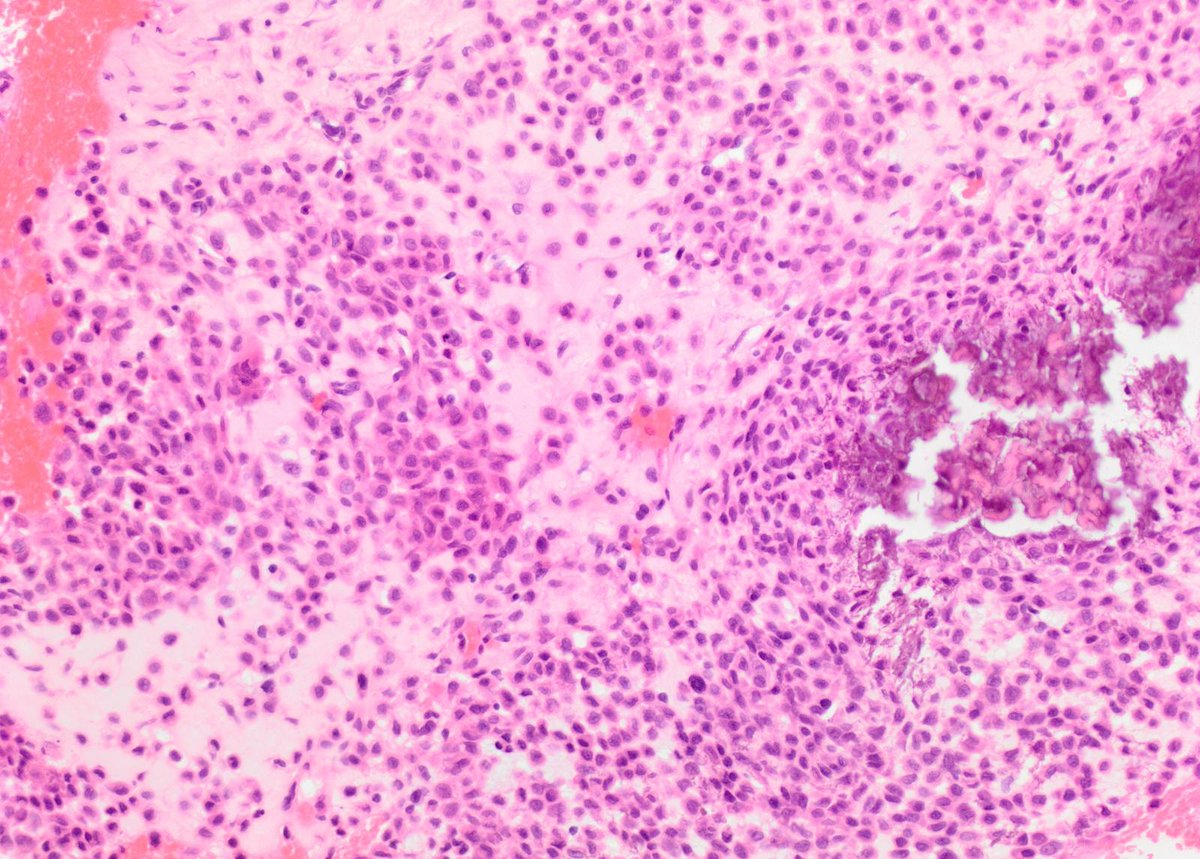

#PathQuiz 🔬🦴

A) Giant cell tumor of bone

B) Aneurysmal bone cyst

C) Chondromyxoid fibroma

D) Chondroblastoma

#Pathology #BonePath #OrthopedicPath

Clue in caption 🧐